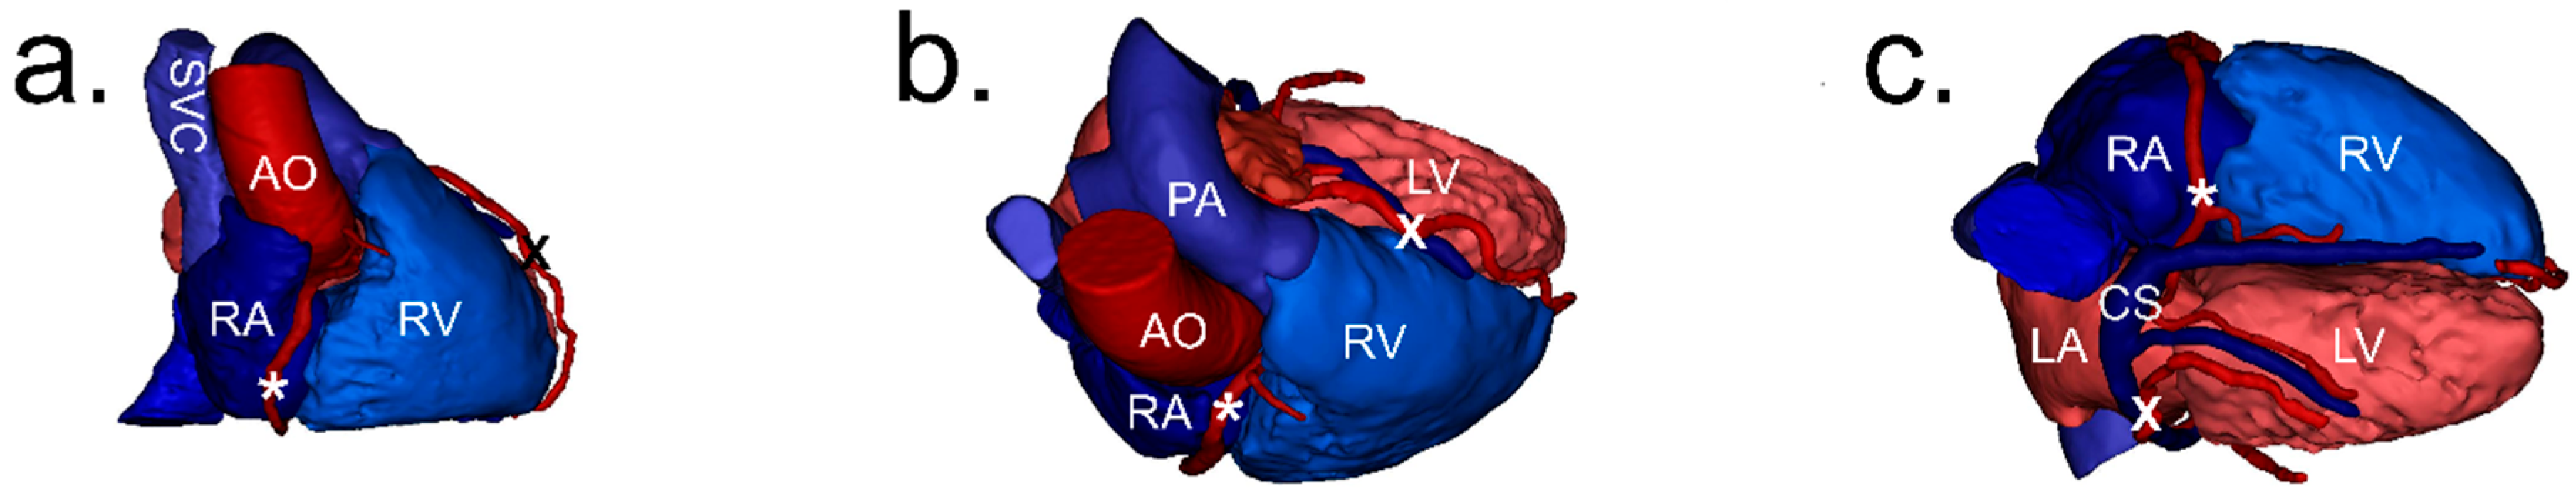

2.2. Image Processing and Analysis

2.3. Definitions

2.4. Measurements